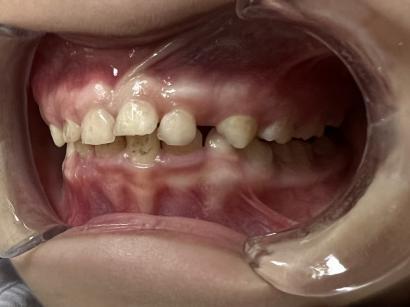

案例二:

治疗前